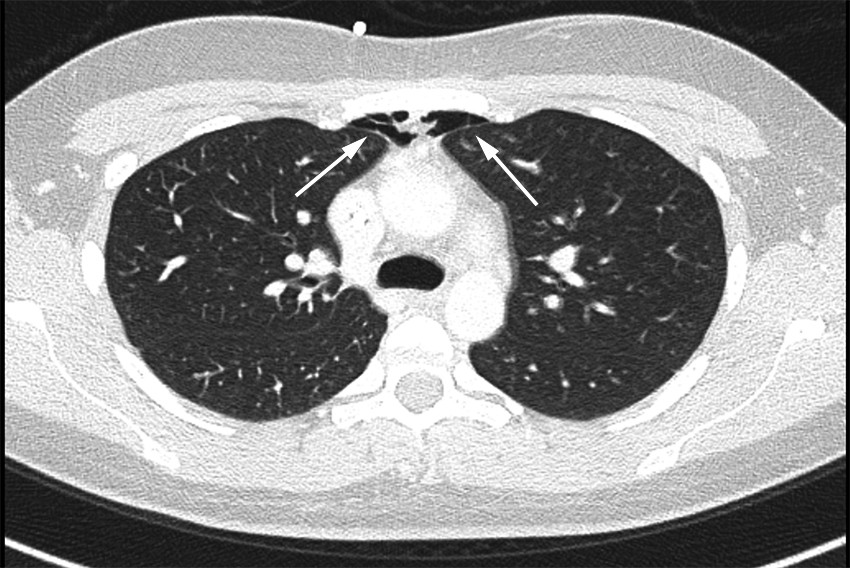

CT-bildet viser stikk-kanal gjennom manubrium sterni (bilde 1: sagittalt, benvindu) og retrosternal luft (bilde 2 på tidsskriftet.no: aksialt, lungevindu) etter aspirasjon av benmarg fra sternum hos en ung kvinne med akutt myelogen leukemi. Benmargsundersøkelsen ble utført standardmessig med sternalnål med skjold på korrekt sted, sentralt i manubrium sterni. Etter at mandrengen ble fjernet, hørtes en surklelyd idet pasienten trakk pusten. Det var ingen motstand ved forsøk på aspirasjon, benmarg lot seg ikke aspirere og pasienten fikk samtidig lett ubehag i venstre skulder. Hun hadde ingen andre symptomer.

CT thorax ble tatt umiddelbart og påviste perforasjon gjennom bakre sternumkorteks og luft retrosternalt. CT-undersøkelsen viste ingen tegn til punksjon av lunge eller pneumotoraks, og man antar derfor at luften ble sugd inn gjennom nålen idet pasienten trakk pusten. Pasienten hadde ingen andre symptomer, og vitalia var stabile. Hun ble derfor behandlet konservativt med sengeleie og oksygen og kunne skrives ut etter 24 timer. Det var ingen ytterligere komplikasjoner, og videre behandlingsforløp for leukemi ble ikke påvirket. I forbindelse med behandlingsforløpet er det tatt gjentatte røntgen toraks, med normale funn.

Som CT-bildene viser, har manubrium sterni en tykkelse på ca. 1 cm. Sternalnål med skjold skal derfor alltid benyttes, og andre deler av sternum enn manubrium sterni skal ikke punkteres. Undersøkelsen kan gjøres også under antikoagulasjonsbehandling og ved alvorlig trombocytopeni (trombocytter under 10 ∙ 109/L) uten transfusjon av trombocyttkonsentrat. Ved mistanke om benmargssykdom foreligger det ingen kontraindikasjoner mot undersøkelsen.